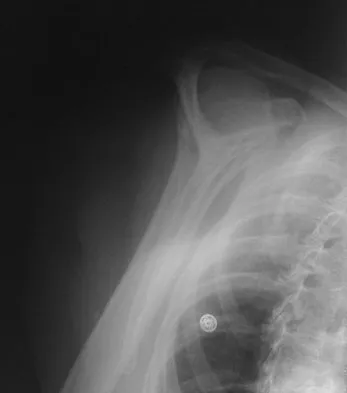

A paraplegic 32-year-old man was pulling himself up in bed by grasping the headboard rails when he felt a pop and immediate pain. A radiograph and CT scan are shown in Figures 2a and 2b. Based on these findings, management should consist of

Explanation

The coracoid process is an essential component of the superior shoulder suspensory complex and must be maintained. Open reduction and internal fixation is recommended if the fragment is large and displaced more than 1 cm. Froimson AI: Fracture of the coracoid process of the scapula. J Bone Joint Surg Am 1978;60:710-711.